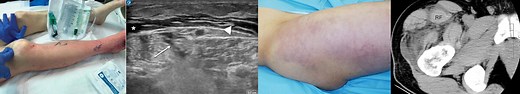

Skin and soft tissue infections (including necrotizing fasciitis)